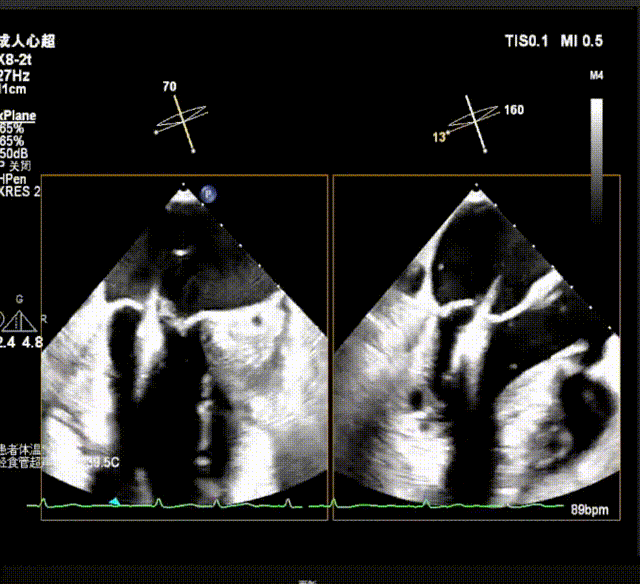

X-plane视窗可见二尖瓣病变区脱垂,重度偏心性返流.

瓣上M/L和A/P调整瓣膜夹,在X-plane进行超声确认,

瓣上进行前后瓣对应夹片确认

瓣上M/L和A/P调整瓣膜夹,在X-plane和3D下反复确认弹道和夹臂方向